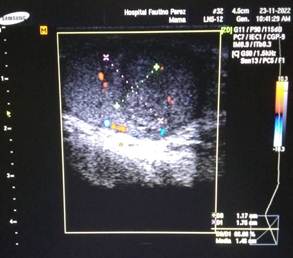

Ecografía Doppler escrotal (Figura 1): informó la presencia de una masa tumoral heterogénea, hipoecoica, localizada en la cara anterior y polo superior del testículo izquierdo, de 10 × 8 mm, con áreas internas quísticas y calcificaciones puntiformes. El estudio Doppler color mostró flujo sanguíneo interno aumentado (hipervascularización), patrón sugestivo de tumor de células germinales (Figura 2). En corte transversal se evidenció el carácter sólido de la lesión, con bordes irregulares y ausencia de sombra acústica posterior (Figura 3).

Figura 2: Ecografía Doppler color, mismo paciente. La masa muestra flujo sanguíneo interno aumentado (hipervascularización), patrón sugestivo de tumor de células germinales.